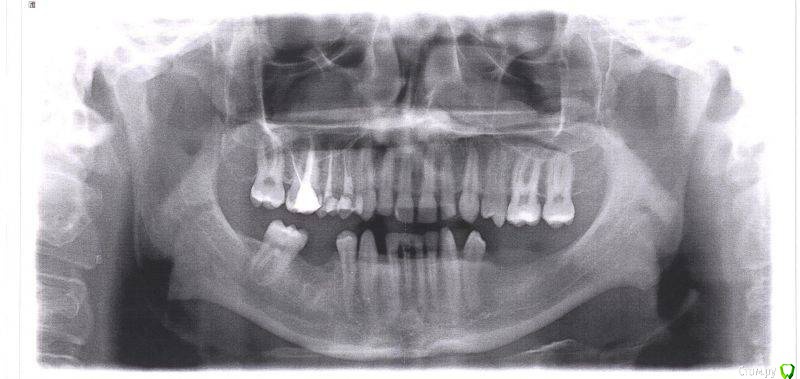

Dionis Опубликовано 13 августа, 2015 Поделиться Опубликовано 13 августа, 2015 Добрый день. Прошел 4х годичный курс лечения ортодонтии. Все готово. Но перед съемом брекетов остро стоит вопрос имплантации. Ортодонт говорит, что нельзя снимать без готовых имплантатов, т.к. могут разъехаться обратно. Прикладываю 4 снимка: до лечения, и 3 снимка КТ с освободившимися местами под имплантаты после лечения. Прошу совета у знающих специалистов:1) В какой последовательности все делать? Очень хочется максимально быстро снять брекеты - сил больше нет(((2) Сколько имплантатов ставить и куда?3) Хватит ли кости справа внизу?4) Посоветуйте, пжста, как выбрать специалиста (-ов), можно в личку. Посетил 3 консультации, две из трех никуда не годятся (доктора не понравились - навязчиво втираются в доверие и ведут себя странно, да и стоимость запредельно выше рыночной). Один доктор понравился, но много негативных отзывов в нете о клинике, как и позитивных, да и видно обилие липовых и левых отзывов, хвалящих самих себя (одни и те же отзывы на разных форумах под разными именами, отзывы с одного айпи и т.д.). Плюс не знаком ещё с ортопедом, который работает в паре... Пока рассматриваю. Буду очень признателен за любую ценную информацию! С уважением,Денис из Москвы Ссылка на комментарий

Dionis Опубликовано 14 августа, 2015 Автор Поделиться Опубликовано 14 августа, 2015 Очень хотелось бы услышать мнения профессионалов по первым трем вопросам:1) В какой последовательности все делать? Очень хочется максимально быстро снять брекеты2) Сколько имплантатов ставить и куда? Ваше мнение очень интересно по поводу нижней челюсти!3) Хватит ли кости справа внизу? Если не хватает, то какой вариант возможен для увеличения (пластика какая именно)? Насколько сложный случай? Судя по КТ, по правому низу в районе 5ки ещё и нерв выходит из челюсти - вчера был на приеме у хирурга, где меня предупредили, что при пластике будет потеря чувствительности из-за разрыва... Насколько это серьезно? Чем чревато в будущем? Совместно с хирургов выработали вариант имплантации 6го с консолью на 5ый. Какие ещё мнения возможны? Спасибо за Ваши ответы,С уважением,Денис Ссылка на комментарий

faity Опубликовано 19 августа, 2015 Поделиться Опубликовано 19 августа, 2015 посмотрел КТ, качество и удобство конечно редкостное...)))проблем не увидел особых, справа импланты, слева импланты и операция по костной пластике. через полгода будете уже ими жевать.только нужно будет КТ переделать, потому что для качественного планирования этого недостаточно.а правильное планирование это половина лечения.по этапам: гигиена(при необходимости), имплантация, через 4 месяца снимать слепки, когда будут готовы коронки- снимать брекеты и фиксировать коронки. но в любом случае надо смотреть Ссылка на комментарий